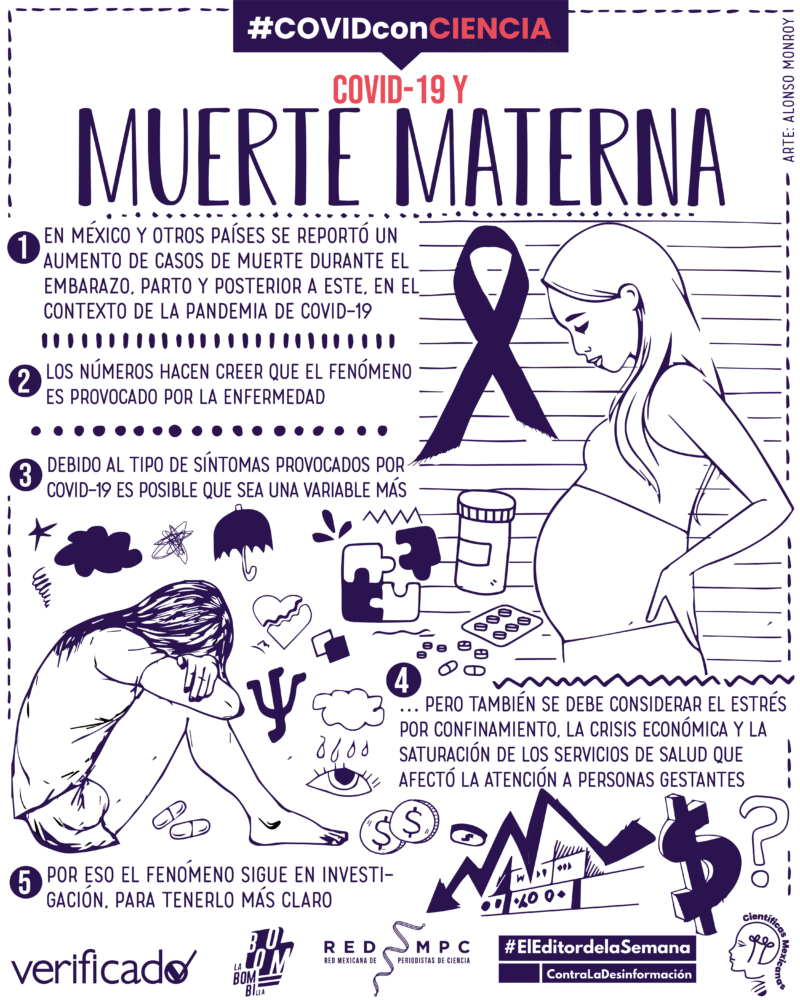

- Diversos países han registrado un aumento de casos de muerte materna y parto prematuro durante la pandemia, y aunque varios medios de comunicación se lanzaron a responsabilizar a COVID-19, lo cierto es que no es posible concluir una relación causal directa.

Pero a partir de la pandemia, esa proporción aumentó. Según los datos presentados durante un seminario por la investigadora Hilda Argüello, del Observatorio de Mortalidad Materna en México, en octubre de 2020 hubo 177 muertes maternas más que en 2019. En la última semana epidemiológica de 2021, reportada por la Secretaría de Salud se reportó un aumento de 18.7%, respecto al mismo mes del 2020.

Otros países han registrado aumentos similares. Por ejemplo, en 2020 Perú registró un aumento del 42% en las defunciones maternas, comparado con el periodo anterior.

Este incremento ha sido justificación para que varios medios como El Economista publiquen notas asegurando que el SARS-CoV-2 es el culpable. Sin embargo, esta información no abunda en las múltiples causas que provocan estos fallecimientos y lo complejo que resulta establecer relaciones de causalidad, es decir, establecer los vínculos que permiten asegurar que un problema es causado por una variable.

Lo que advierten varios estudios es que falta más investigación dedicada a este grupo de riesgo de la pandemia, que no solamente involucre los aumentos de casos, sino explicaciones desde la epidemiología y la inmunología, hasta el acceso a los servicios de salud y las condiciones socioeconómicas de cada población.

Dicho con total claridad: existen estudios que muestran una posible relación entre la COVID-19 y el aumento de casos de muerte materna en México y el mundo, pero dejan claro que existe más de una causa.

Sumado a las comorbilidades que sufre la población mexicana, la respuesta multiorgánica que produce la COVID-19, y la falta de atención médica oportuna durante la pandemia (causadas por la reconversión y saturación hospitalaria y el miedo al contagio), el registro de muertes maternas durante una emergencia sanitaria que requiere mecanismos estadísticos propios, supone un reto importante para la salud pública.

Como puede verse, establecer las causas de muerte materna es un asunto complejo, que implica diversas variables, a las cuales durante los últimos dos años se sumó la pandemia, lo que aumentó el nivel de complejidad.